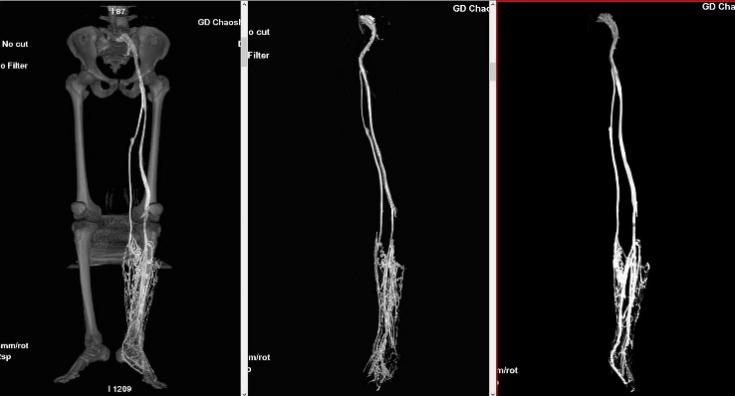

我们的服务项目涵盖了全身各部位的影像检查,包括但不限于:头部、颈部、胸部、腹部、盆腔、四肢等部位的CT、MRI、DR等检查。我们还提供特殊的影像检查服务,如血管造影、MR多功能成像等。例如:

血管造影: